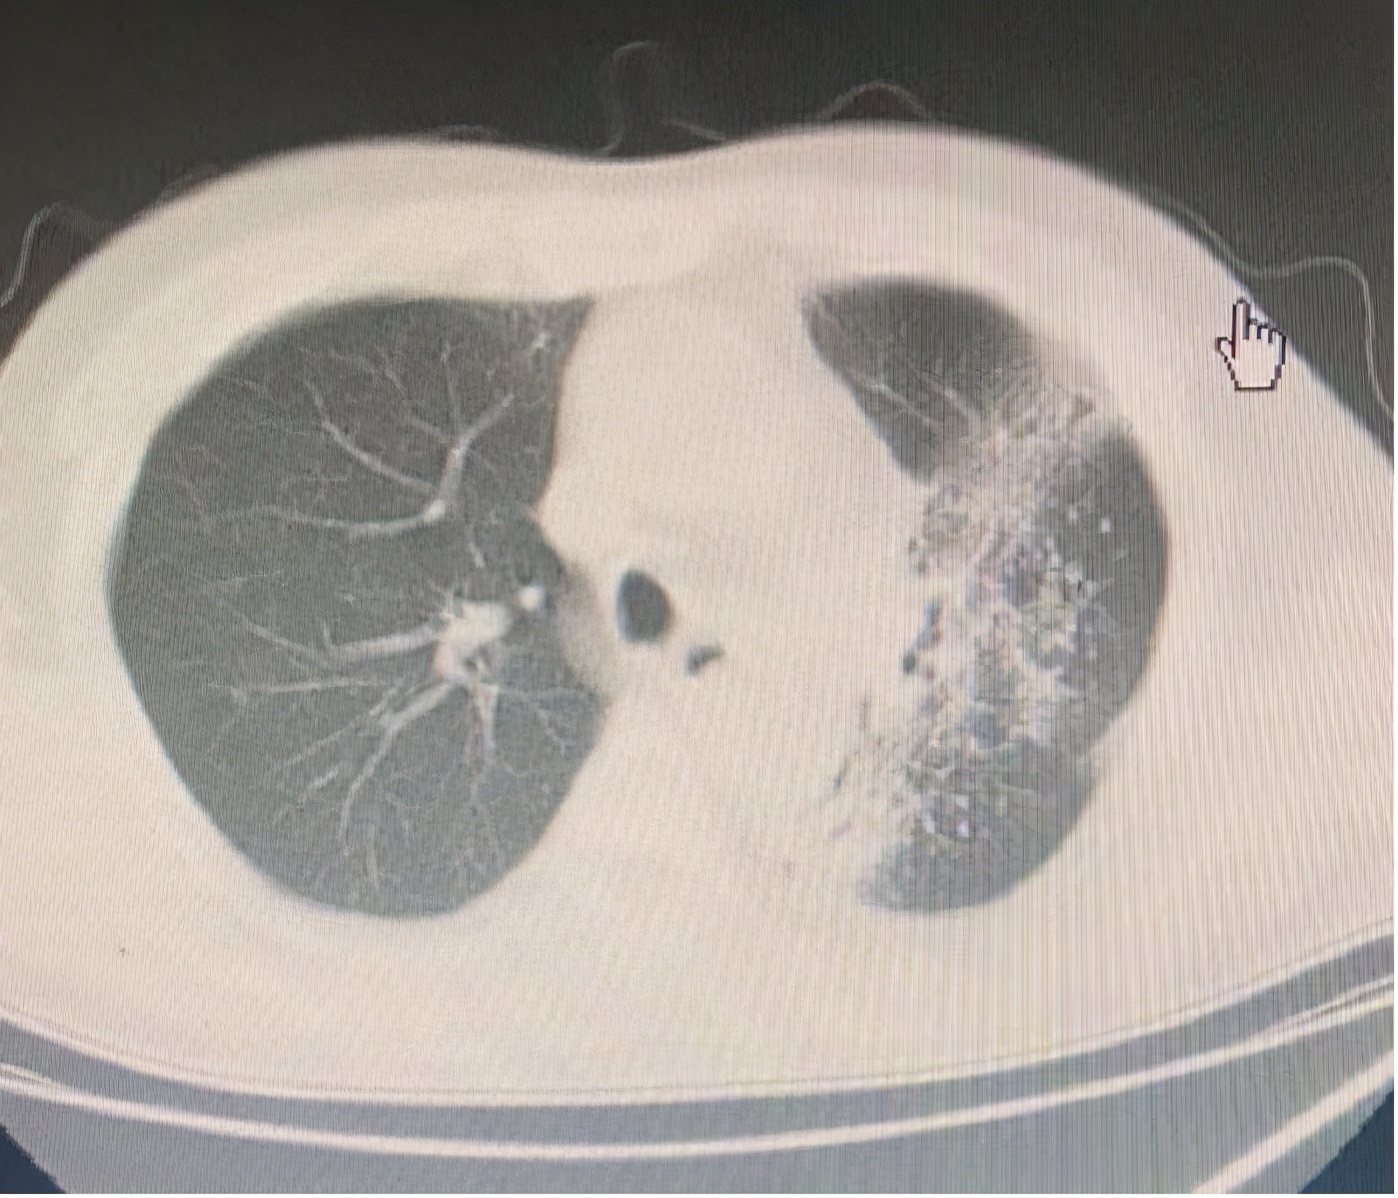

李某某今年56岁,因反复咳嗽咳痰、胸闷3月余于2020年4月来我院肿瘤科住院。胸部增强CT:“左肺中央型肺癌并左上叶阻塞性不张,纵隔淋巴结肿大”。电子支气管镜见左上叶新生物,病理及免疫组化:(左上新生物)“恶性肿瘤,符合鳞状细胞癌”。基因检测:未见热点基因突变,PD-L1阴性。予以化疗3程后,咳嗽,咳痰,胸闷等症状好转,左上肺肿瘤缩小,2取得了较好的治疗效果,2020年06月予以胸部放射治疗,治疗顺利。2020年08月提示左上肿块缩小,同时可见磨玻璃样影及小片、索条状影,与放射野相仿,考虑急性放射性肺炎。给予抗炎治疗后,左肺磨玻璃样影明显吸收。然后继续抗肿瘤治疗。

两张图片对比分析,典型的射野途径上产生的放射性肺炎,患者经抗炎治疗后好转。